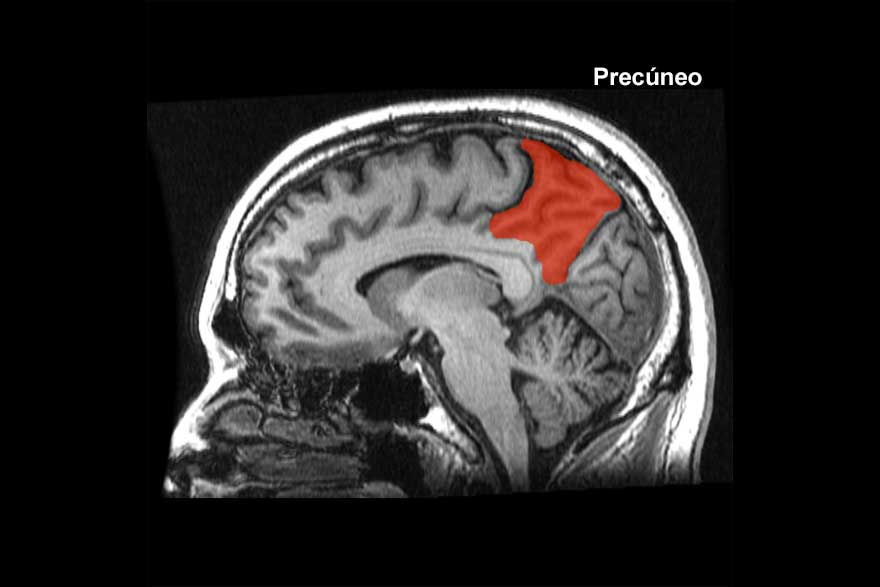

Una zona del cerebro llamada precúneo, situada en el lóbulo parietal, está específicamente involucrada en el procesamiento de intenciones relacionadas con uno mismo. En concreto, con relaciones causa-efecto que no se basan en experiencias previas, sino solo en ideas y que se atribuyen irracionalmente a la persona que lo piensa.

Juega un papel importante en la creación de la propia historia, en la responsabilidad de los actos que se cometen. Está más activado en las personas que sufren este tipo de rumia así que, con facilidad, creen que lo que piensan puede tener repercusión en el mundo real.